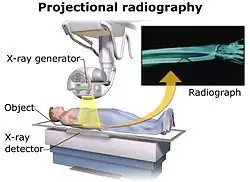

Projectional radiography

The creation of images by exposing an object to X-rays or other high-energy forms of electromagnetic radiation and capturing the resulting remnant beam (or "shadow") as a latent image is known as "projection radiography". The "shadow" may be converted to light using a fluorescent screen, which is then captured on photographic film, it may be captured by a phosphor screen to be "read" later by a laser (CR), or it may directly activate a matrix of solid-state detectors (DR—similar to a very large version of a CCD in a digital camera). Bone and some organs (such as lungs) especially lend themselves to projection radiography. It is a relatively low-cost investigation with a high diagnostic yield. The difference between soft and hard body parts stems mostly from the fact that carbon has a very low X-ray cross section compared to calcium.